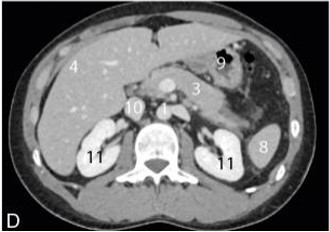

Je t'ai mis un schéma et une coupe axiale d'un scanner abdominal légendé pour que tu visualises au mieux :

Voici les légendes : 3 = Pancréas / 4 = Foie / 8 = Rate / 9 = Estomac